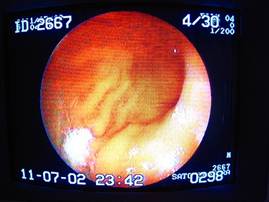

胃の中に入ったところ。

(大彎部~幽門に向けて)

ん? なにやら怪しいものを発見。もう少し接近してみましょう。

画面左上に、もやもやした異物を確認。

これから摘出を試みます。